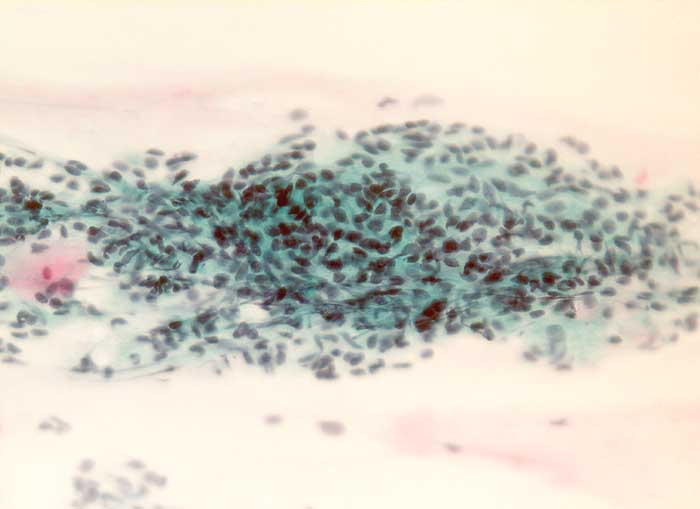

PathoPic ID 6116 - endometriale Stromazellen

endometriale Stromazellen

Normalbefund

Zervix

Genitalorgane, weiblich

Zervixabstrich: Verband spindeliger Zellen mit dunklem regelmässigem Chromatin und schmalem Zytoplasmasaum.

Zytologische Diagnose: reichlich endometriale Zellen, wahrscheinlich Stromazellen, unverdächtig.

Zytologie

320